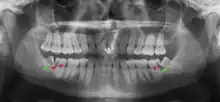

Impacted wisdom teeth are classified by their direction of impaction, their depth compared to the biting surface of adjacent teeth and the amount of the tooth's crown that extends through gum tissue or bone. Impacted wisdom teeth can also be classified by the presence or absence of symptoms and disease. Screening for the presence of wisdom teeth often begins in late adolescence when a partially developed tooth may become impacted. Screening commonly includes a clinical examination as well as x-rays such as panoramic radiographs.

Impacted wisdom teeth are classified by the direction and depth of impaction, the amount of available space for tooth eruption, and the amount of soft tissue or bone (or both) that covers them. The classification structure helps clinicians estimate the risks for impaction, infections and complications associated with wisdom teeth removal.[6] Wisdom teeth are also classified by the presence (or absence) of symptoms and disease.[7]

One review found that 11% of wisdom teeth will have evidence of disease and are symptomatic, 0.6% will be symptomatic but have no disease, 51% will be asymptomatic but have disease present and 37% will be asymptomatic and have no disease.[7] Impacted wisdom teeth are often described by the direction of their impaction (forward tilting, or mesioangular being the most common), the depth of impaction and the age of the patient as well as other factors such as pre-existing infection or the presence of pathology (cysts, tumors or other disease).[5]: 143–144 Each of these factors is used to predict the difficulty (and rate of complications) when removing an impacted tooth, with age being the most reliable predictor[8] rather than the orientation of the impaction.[9]